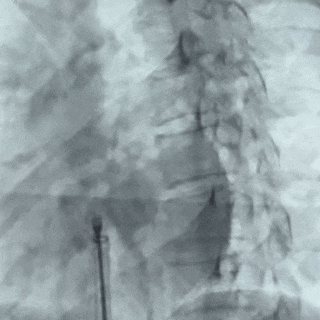

DSA下将前4个Mark点推出鞘管后,轻拉成型线使盘面成型

将输送系统整体后撤贴靠房间隔,超声下可见左盘贴合在房间隔上

后撤鞘管,轻轻牵拉钢缆行牵拉试验,DSA下确认5个Mark点整体随钢缆移动,判定封堵器锁定成功

锁定后造影

锁定后造影,确认封堵器位置正确,无残余分流

逆时针旋转钢缆释放封堵器,DSA下可见5个Mark点呈 “T”字型聚拢形态